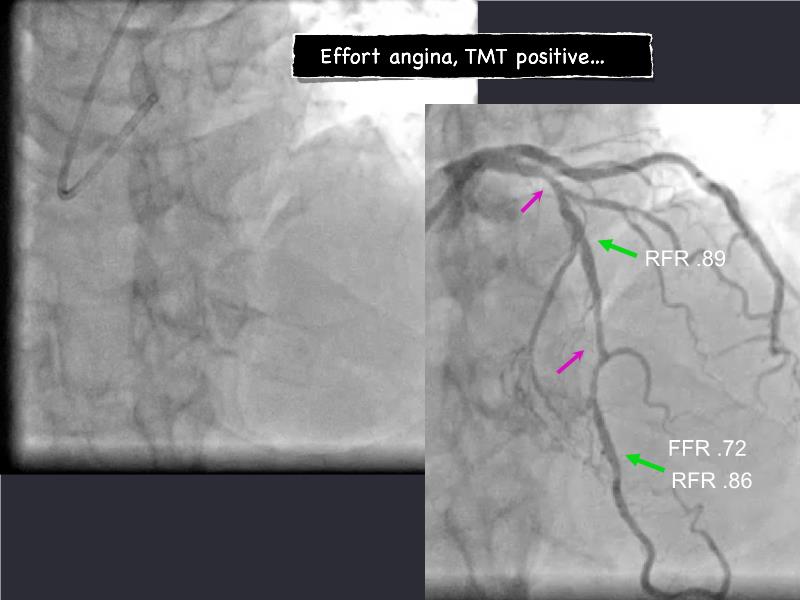

- To understand novel tools and techniques for effective management of bifurcation lesions and long diffused lesions using dedicated stenting solutions